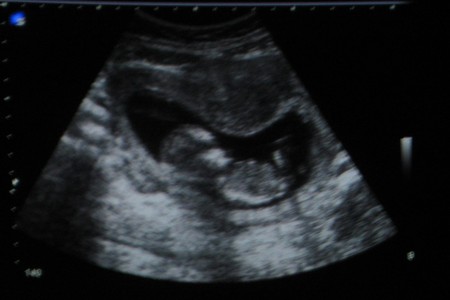

Мой масик зашевелился) Мой младший масик. Я, конечно, думала, что второй раз ребенок подаст признаки бурной деятельности раньше, но в 13 недель... на это я не расчитывала. Это было всего два раза. Будто маленькие-маленькие ножки пробежали внутри по животу. Хочу уже, чтоб выросло пузо и малыш активно ворочался))) Еще хочу накупить на лето вещей для беременных. А то прошлый раз с животом ходила зимой - и не видно было почти.